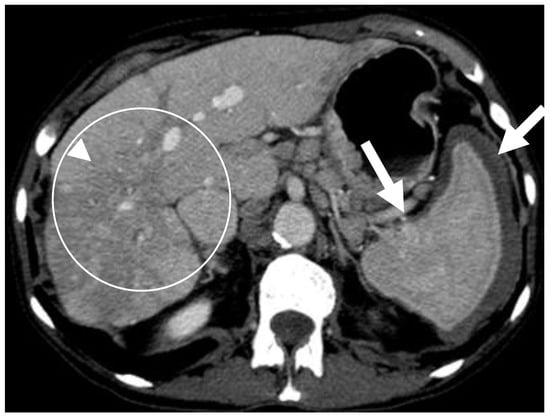

6.2.2. Liver and Spleen